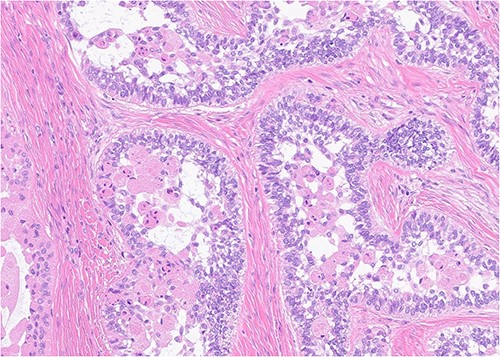

A 52-year-old male presented with a 4-month history of right lower lateral lip swelling and dental complaints. On physical examination, there was a large right mandibular mass with several floating teeth extending from the symphysis to the angle (Fig. 1). The patient’s history was notable for hypertension and a 36-pack year smoking history. He denied any other concerning symptoms. Computed tomography (CT, Fig. 2) imaging demonstrated at large heterogeneous, multiloculated, expansile lesion of the right mandible. An incisional biopsy was performed, and results demonstrated epithelial tumor islands with columnar cells exhibiting peripheral palisading, stellate reticulum-like areas, granular cells, and reverse polarization (Fig. 3). Following diagnostic confirmation of multicystic granular cell ameloblastoma, the patient underwent successful surgical resection and reconstruction. Final pathology showed a 5.0-cm granular type conventional multicystic ameloblastoma with negative surgical margins. At time of report, 7 years after resection, our patients is alive with no evidence of recurrence.

Histopathology (400×, H&E strain) demonstrating characteristic granular cell ameloblastoma features such as epithelial tumor islands with columnar cells exhibiting peripheral palisading, stellate reticulum-like areas, granular cells, and reverse polarization.

Pathological analysis serves as the basis for final diagnosis of these odontogenic tumors. There are at least six histopathological patterns associated with conventional multicystic ameloblastoma. The most common is of the conventional multilocular type with a follicular histological pattern, which is consistent islands of odontogenic epithelium in fibrous connective tissue, classic peripheral palisading, and stellate reticulum-like areas. Our patient was of the rarer granular type with a presentation consistent with stellate reticulum-like cells having large eosinophilic rounded or polyhedral granular cells. Interestingly, microscopic pattern has no documented prognostic significance [4].